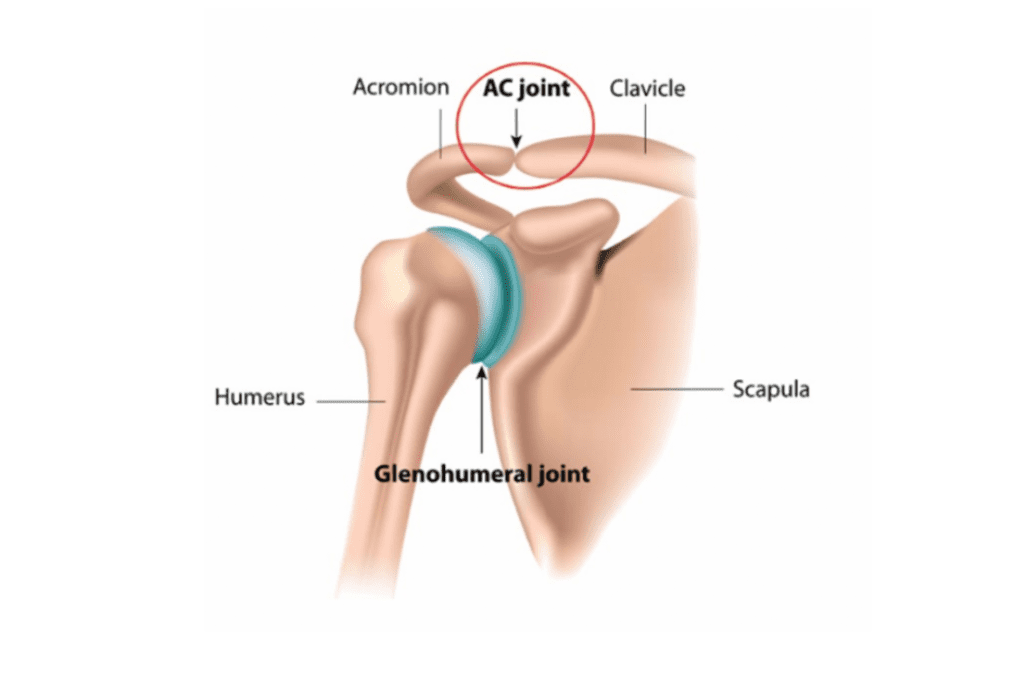

Glenohumeral ligament: анатомия и функции плечевого сустава